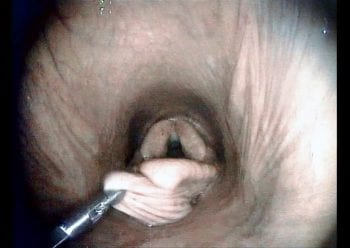

A transendoscopic lance was used to penetrate the cyst and aspirate approximately 15ml of serous fluid (Figure 2). This partially deflated the cyst, easing manipulation and assisting in dissection. With endoscope in situ, curved bronchoesophageal grasping forceps were passed through the contralateral nasal passage and used to manipulate the cyst (Figure 3). A transendoscopic diode laser was used to excise the cyst en bloc, along with the overlying subepiglottic mucosa using a contact technique (Figures 4 and 5). Following excision, topical dexamethasone sodium phosphate (total 20mg) was applied to the surgical site.